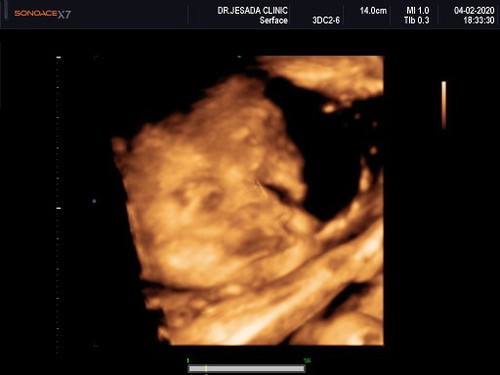

อยากเจอหน้าแล้วแม่ๆทีมพฤษภามาอวดน้องกันค่ะ

แม่ซาวด์ดู4มิติ เเพงมั้ยค่ะ

ของแม่ฝากคลินิกคุณหมอซาวใหเประจำค่ะไม่ได้เสียเพิ่ม